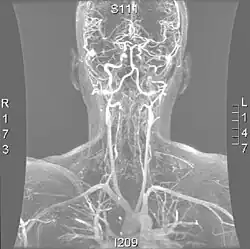

| Método de diagnóstico | Angiotomografia, Angiografia por ressonância magnética |

Os métodos mais modernos envolvem angiografia por tomografia computorizada, denominada angiotomografia (ATC ou angio-TC) — e ressonância magnética (RM). Estes métodos requerem uma menor quantidade de contraste e não são invasivos. A angiografia por TAC e a angiografia por RM são mais ou menos equivalentes quando usadas para diagnosticar ou excluir uma dissecção da artéria vertebral.[13] A ATC tem a vantagem de mostrar certas anormalidades mais cedo, tende a estar disponível fora do horário de expediente e pode ser realizada rapidamente.[1] Quando a angiografia por RM é usada, os melhores resultados são obtidos no cenário T1[2] usando um protocolo conhecido como "supressão de gordura".[3] A ecografia Doppler é menos útil, pois fornece poucas informações sobre a parte da artéria próxima à base do crânio e no forame vertebral, e qualquer anormalidade detectada na ecografia ainda exigiria confirmação através de um TC ou RM.[1][2][3]